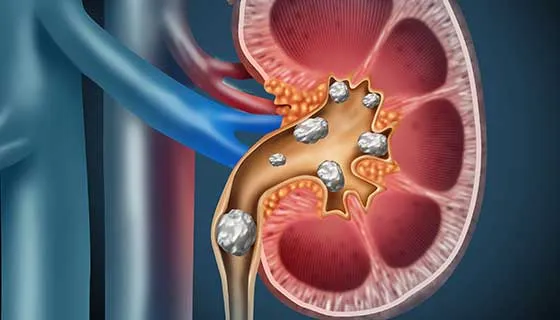

Injúria Renal Aguda (revisão Lancet 2025)